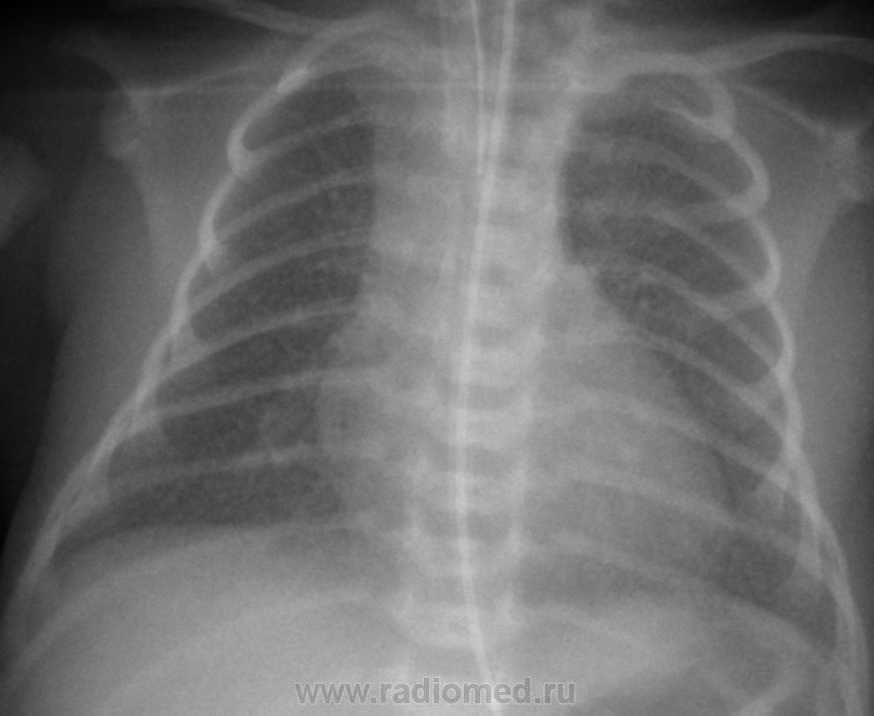

Снимок от 5.03.10г.

Трудно сказать, но мысли в пользу интерстециальной пневмонии, преимущественно вирусной этилогии, однако ребенку провели курс антибактериальной терапии, на данный момент он самостоятельно дышит, клиники ни какой нет, динамика положительная. Во время прведения курса лечения 9.03. был сделан рентген-контроль, где  динамика положительная была.

1.По диссеминации похоже динамика положительная.

2.Но не складывается ли впечатление о появлении сливной инфильтрации справа в базально-медиальном отделе, ближе к корню?

3.В нерешительностиВозможно присоединение бактериального компонента на фоне вирусного поражения....

Стараюсь вообщем то отслеживать ход демонстрируемых случаев, но поскольку поток пациентов вариабильный, ни как не могу сконтактироваться с неонатологами, на данный момент по электронной истории, состояние средней тяжести связано с незрелостью ребенка. По снимку в динамике хочу согласиться с Вами что есть затемнение в прекорневой зоне справа, однако по поводу забора анализов ПЦР на ЦМВ, мне не известно.